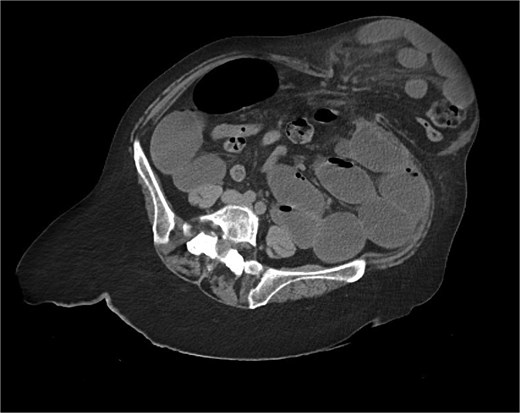

Immediate action involved removing fluid from the gastric band and inserting a nasogastric tube, which was slightly difficult. Only 200 ml of gastric content was drained, and no air was present (indicating that it was not in the stomach). Given the possibility of anatomical pathology or obstruction at the gastroesophageal junction (GEJ), we avoided excessive force when inserting the tube to prevent iatrogenic esophageal perforation. A computed tomography (CT) scan with liquid-soluble contrast media showed that the contrast did not pass beyond the band. The scan also revealed massive gastric dilatation, as well as dilation of the esophagus proximal to the band (Figs 2–4).

CT axial view—contrast media in distal esophagus did not pass to the stomach.